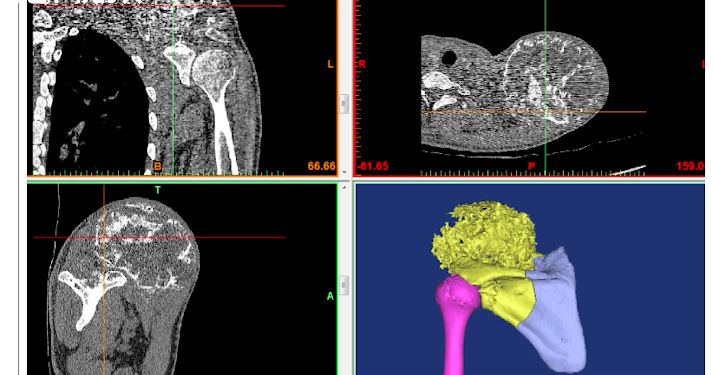

▲檢查結果。(圖/翻攝自秒拍)

經過規範化新輔助化療後,肖建如團隊為小傑實施了腫瘤enbloc完整切除,手術歷時8個多小時。手術中根據3D打印導板引導精確截骨,3D打印假體重建肩關節,腫瘤達到局部徹底切除,希望可以達到良好的局部控制,肩關節的功能也能夠保留一部分。